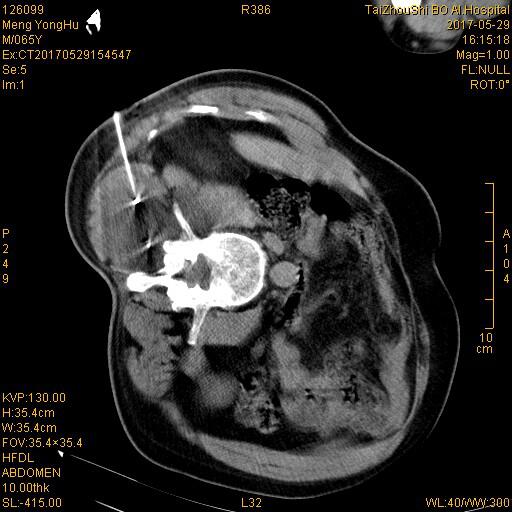

冷冻后即刻评估疗效:冰球(脂肪密度)